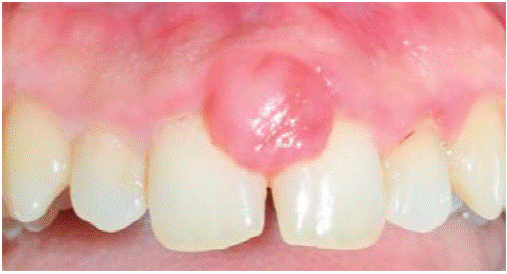

Al examen clínico se observa lesión gingival inflamatoria a nivel de las piezas 1.1 y 2.1, de aproximadamente 9 X 9 mm, cubriendo un tercio de la corona clínica, de consistencia firme, lobulada, textura rugosa, sangrante ante el estímulo y asintomática (Figura 9). A la evaluación periodontal no presentaba bolsas periodontales, sin embargo, se observó presencia de placa, obteniéndose un índice de higiene oral (O'Leary) de 50%.